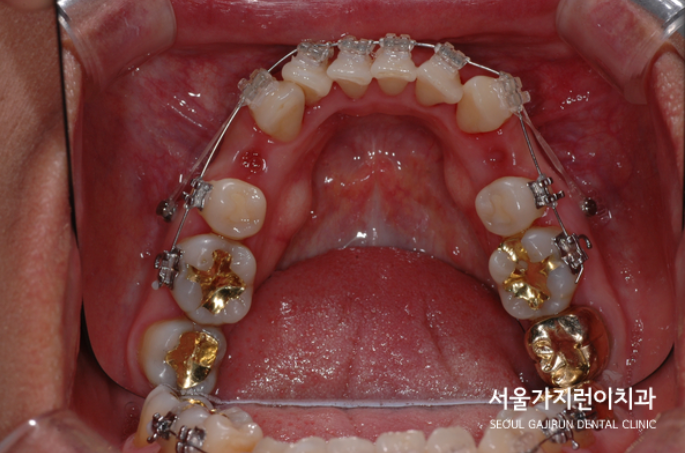

그래서 서울가지런이치과 교정과 의원에서는 치아를 발치한 후에 상하악 치아배열을 바로 잡기로 했는데요. 어금니 교합을 정상으로 만들기 위해서는 상당히 많은 치아 이동이 필요한 상태였습니다. 치아이동에 사용된 장치로는 전방 이동을 위한 미니스크류와 레버암이 있는데요. 치아를 이동시키면서 다른 치아가 움직이지 않도록 지지대 역할도 하면서 충분한 이동에 도움이 될 수 있도록 레버암까지 동원해 힘의 작용방향과 크기를 조절하였습니다.

주걱턱도 개선해야 했지만 정상교합으로 돌려놓기가 쉽지 않았는데요. 환자분의 경우 치료 1년 후 안정적으로 교정치료를 마쳤으며 6년이 지난 지금까지 안정적인 상태를 유지하고 있었습니다. 이 사진을 보면 교정이 잘 이루어져 재발하지 않았다는 것을 확인할 수 있는데요.